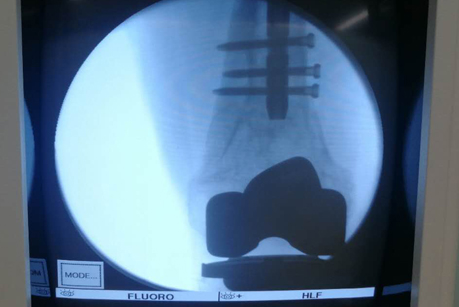

术中影像

在手术之前,首先做股骨全长薄层扫描CT,将患者股骨影像及数据搜集并记录下来,通过3D打印技术制作出一个1:1比例的股骨“复制品”,它的直径、长短、髓腔形态都与患者真实情况完全相符,甚至患者骨骼上每一块凹陷与凸起,每一点纹理和痕迹都呈现得一清二楚。然后通过在体外对模型进行模拟手术操作,准确制订出了髓内钉的入针点、长度、直径,精确计划出远端锁钉准确位置。手术时,按着术前的设计顺利完成了手术,大大缩短了手术时间,减少了对患者的创伤。术后影像骨折解剖复位,锁钉位置精准无误,术后患者顺利康复。